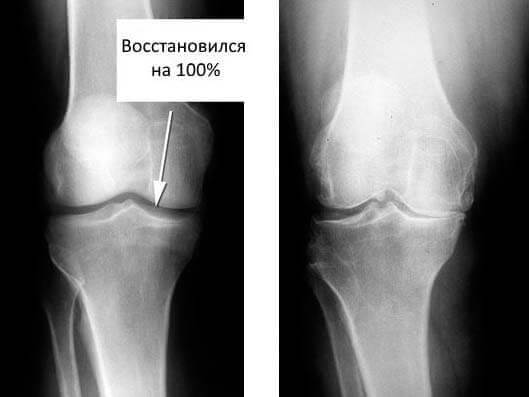

35 кун: таҳлил топширдим ва рентген қилдирдим. Артроздан ҳеч қандай из ҳам қолмаган! Бўғимлар тўқималари ҳудди 30 ёшдаги йигитдек. Шифокор ўтган сафарги рентгенда камчилик ёки тушунмовчилик бўлгани сабабли, артроз ташхиси хато бўлган бўлиши мумкинлигини айтди.